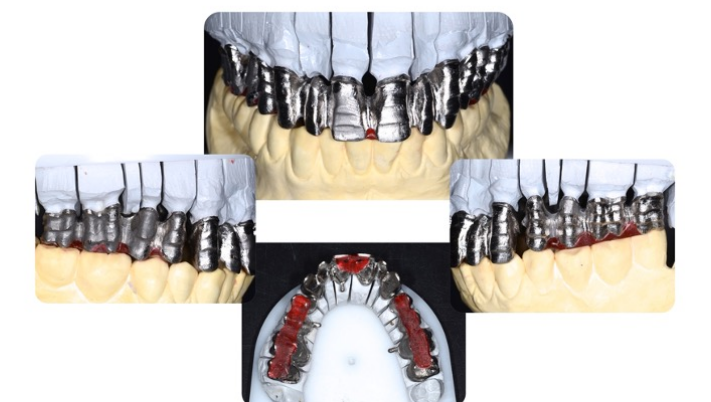

Per ottenere questi risultati una riabilitazione protesica è formata da 4 differenti porzioni: il pilastro protesico cioè il dente o l’impianto, il framework o mesostruttura, per esempio, la porzione di metallo degli scheletrati (Fig.5), il corpo protesico, come la porzione di resina rosa nella protesi totale e gli elementi dentari di sostituzione [20] . Nel caso della corona singola il corpo protesico e l’elemento di sostituzione sono riuniti nella corona stessa.Fig.6.

Per eseguire una struttura anatomica corretta, è necessario occupare i volumi adeguati e completi degli elementi finiti, sia che si lavori in analogico (Fig.11) che in digitale (fig.13).

In analogico eseguiremo una riduzione guidata dalle mascherine che ci aiuteranno a realizzare i corretti spessori per il materiale estetico (Fig.12 ).

Grazie a questo protocollo potremo realizzare framework metallici, fresati o fusi, su pilastri naturali o implantari che verranno rifiniti dopo la prova per ottimizzare gli spazi Fig.16